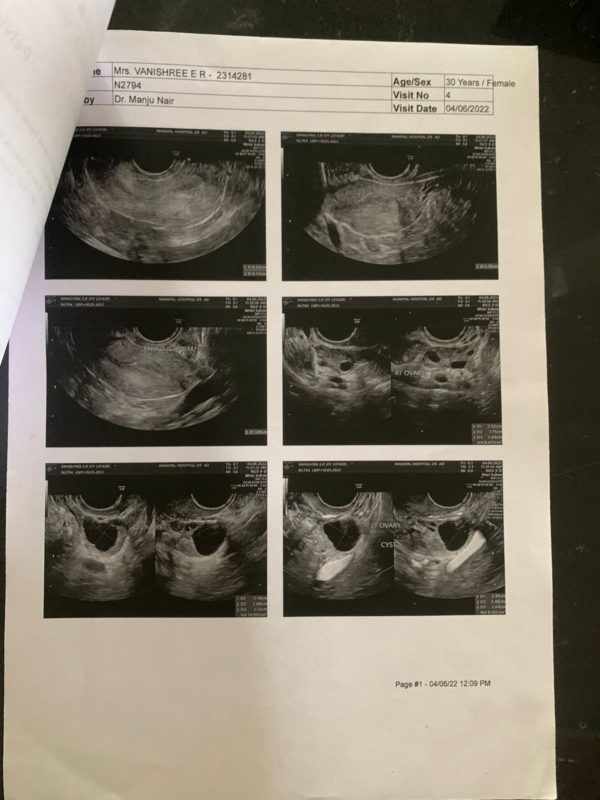

The images of the USG scan shows

1. Pre-

2. Post-

USG Reports

Post – Right ovary appeared normal Both fallopian tubes are visualized in their entire length and are normal.